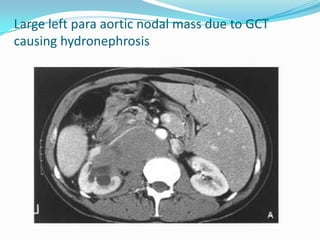

Large left para aortic nodal mass due to GCT

causing hydronephrosis

Large left paraaortic nodal mass due to GCT causing hydronephrosis